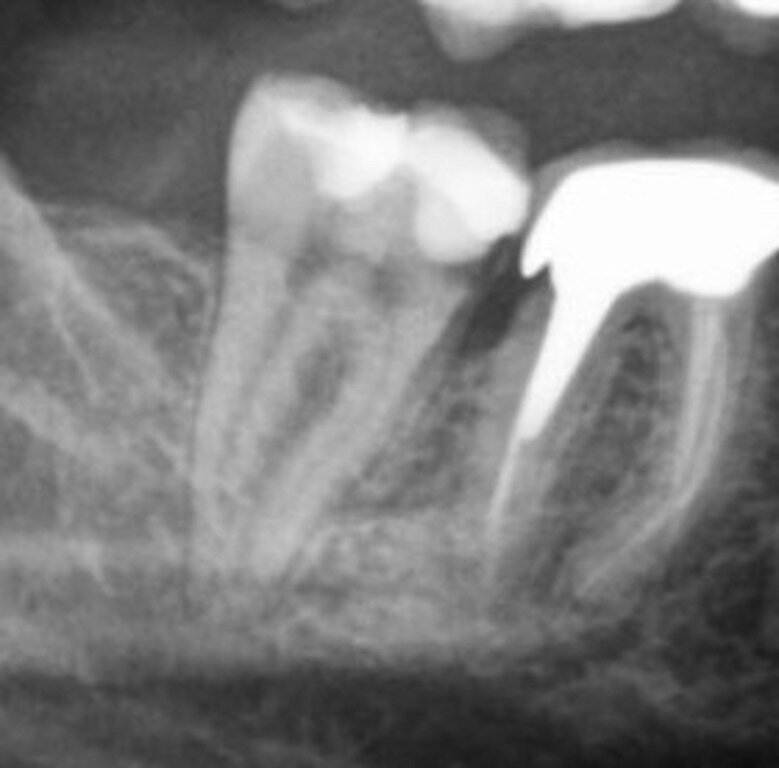

1) Неправильно поставленные пломбы или протезы, с нависающими или острыми краями, которые затрагивают десну.

Ну думаю здесь все понятно, всегда в таких случаях приходите на корректировку, потому что иначе это может перерасти в хроническую травму, которая в свою очередь является отправной точкой для дальнейшего развития патологии.

На рентгене мы видим явный нависающий край коронки